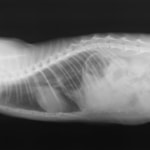

術前のレントゲン

■ 症例:10歳 ドーベルマン 主訴:突然の嘔吐、虚脱